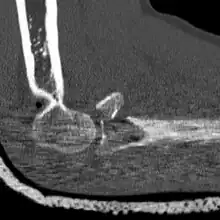

CT scan demonstrating the Mason type III radial head fracture -

CT scan showing a radial head fracture -